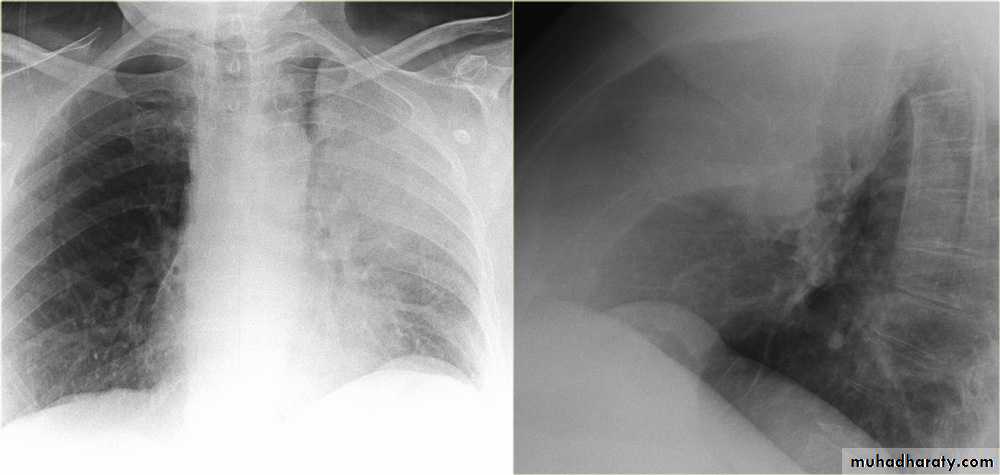

Patient with fever, rigor and dyspnea